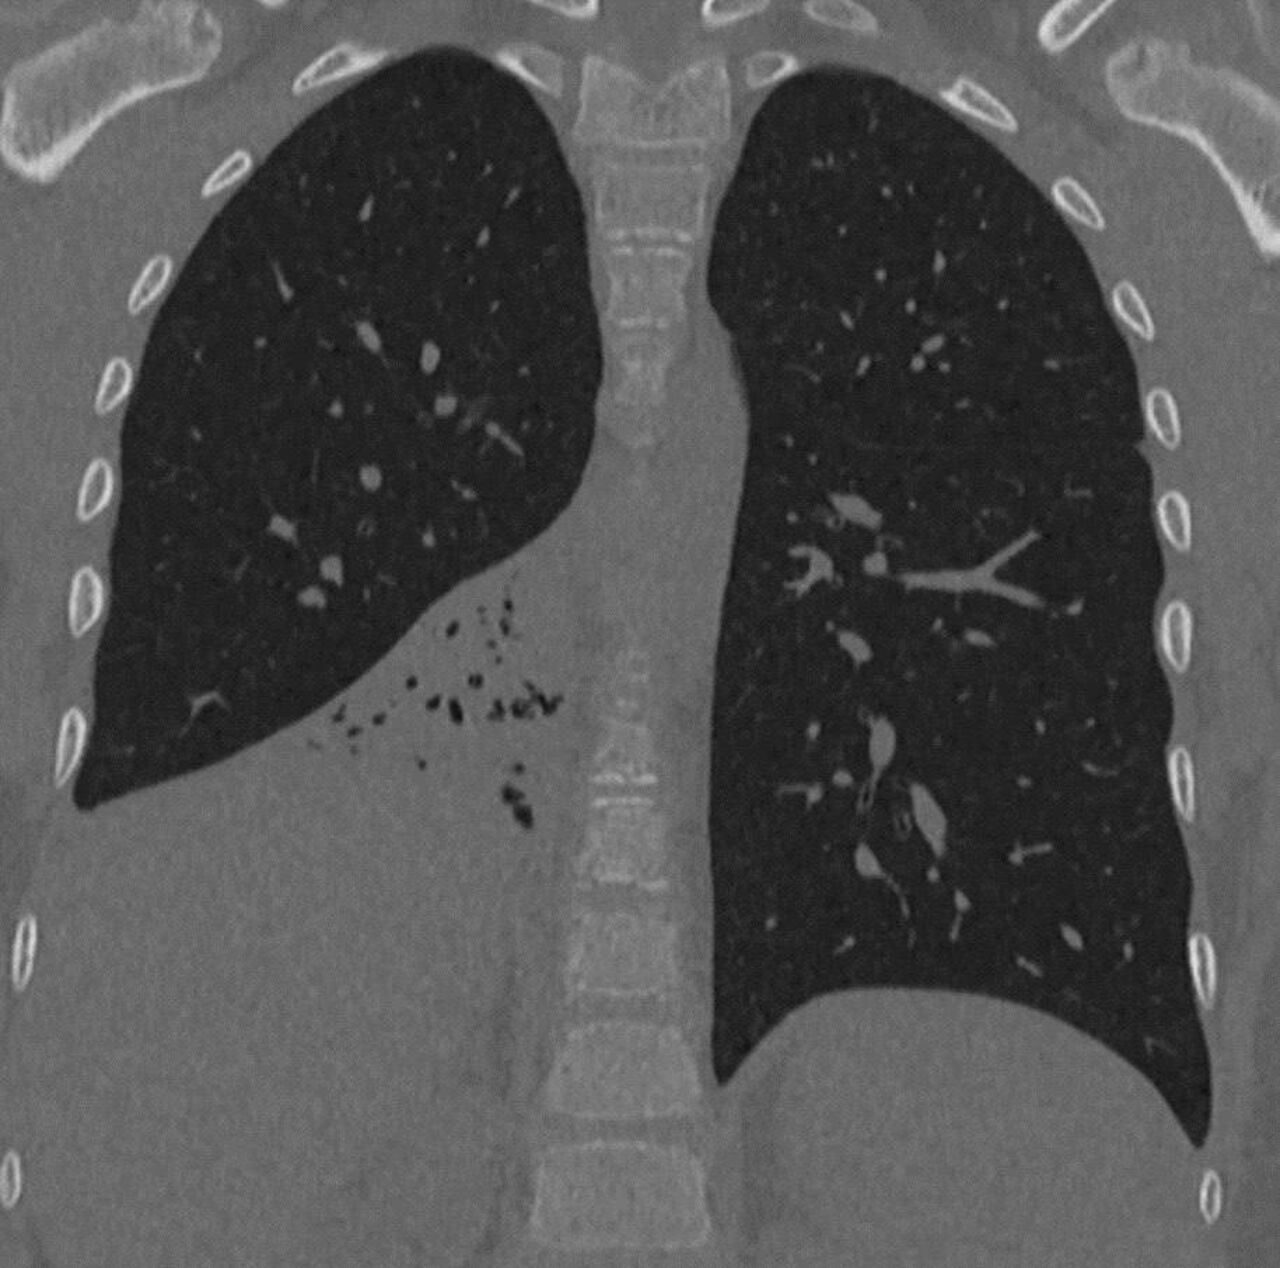

Медики провели осмотр, в ходе которого выяснили, что у школьника воспалено правое легкое, его вентиляция нарушена. Оказалось, что причиной этого стал посторонний предмет в бронхах – маленький пластиковый колпачок. Мальчик признался, что случайно вдохнул его полгода назад.